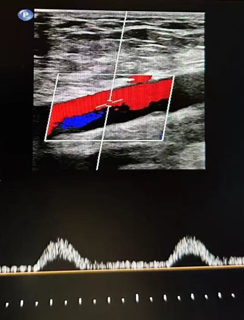

心功能室王璇主任会诊后,结合异常血流动力学特点,将目标锁定超声探查难点——胸骨遮挡的降主动脉胸段!建议行主动脉CT血管成像(CTA)检查以明确诊断。

CTA确诊:罕见畸形浮出水面

CTA结果印证了王璇主任的判断:患者降主动脉胸段(距锁骨下动脉约10厘米处)存在一处少见的先天性局部缩窄,并伴有远端扩张。这正是导致患者下肢血流灌注不足、多年感觉发凉的“元凶”——降主动脉缩窄,一种少见的血管发育畸形!